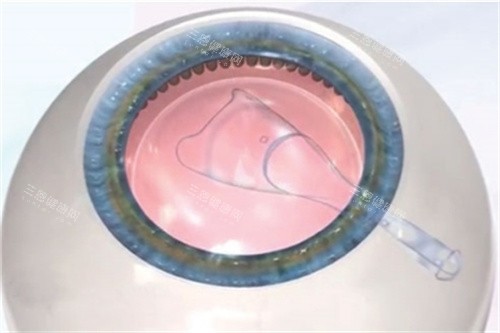

第3步:装晶体(5分钟)

折叠的晶体通过注射器推进眼内,再用调位钩展开。上海新视界眼科的王医生透露:"比较考验技术的是调整角度,散光晶体要精细对齐,差1度都会影响结果。"

第4步:定位(2分钟)

用显微镜观察晶体位置,确认无偏移、无褶皱。杭州明视康眼科的郑主管笑称:"这时候就像给眼睛'戴美瞳',得确保既舒服又好看。"